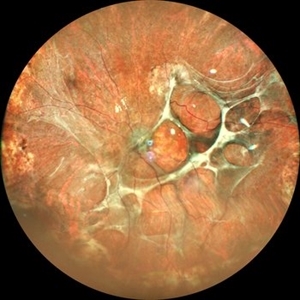

Von Hippel-Lindau Syndrome

Jul 12 2021 by Akansha Sharma

Color photo montage of a 19-year-old female with Von-Hippel-Lindau syndrome.

Photographer: Dr. Akansha Sharma-Retina Foundation, Ahmedabad

Condition/keywords: angioma, Von Hippel-Lindau